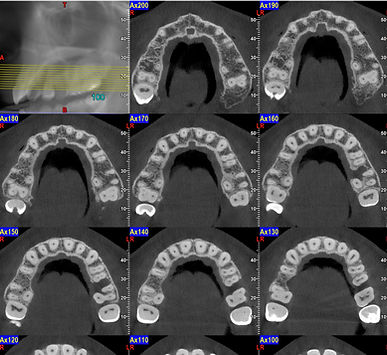

3D CBCT IMAGING

Every CBCT scan is post processed by our highly trained staff. They are experts in CBCT image capture, data management, image formation, and 3D post-processing techniques. Our image surveys support all dental modalities with the best diagnostic image surveys for any CBCT machine.

The CBCT, characterized by cone-beam X-rays, allows very detailed images of bone tissues to be obtained in a very short time. These images can be used in various fields such as implantology and maxillofacial surgery.